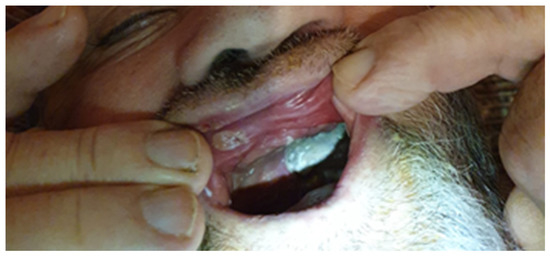

2. Case Report